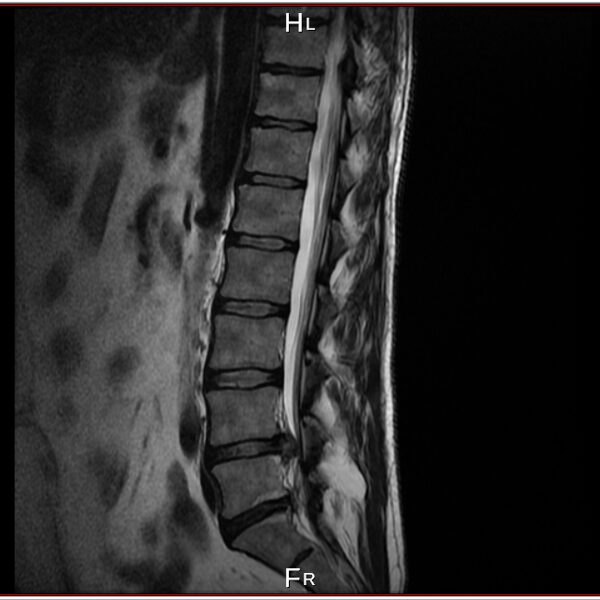

I have a lower spine problem, herniated disk and was using acupuncture (acupuncture is really good to control your musculus and controlling you like a robot) treatments with a Chinese doctor, first time all was perfect, but second time looks like happen mistake, you will be able to see this on pictures from private MRI scan– nuclear magnetic resonance that I have organised for myself. My left leg was just bone and skin, I lost all the musculus, because was not able to feed the main nerve responsible for keeping the proper function of the whole leg – I was parallelized. Pain is 24/7, 10 out of 10. At Royal infirmary hospital Edinburgh where I was hospitalized was giving me crazy amount of pain killers and very strong, that never helped. The doctors at the hospital they did great job providing me with modern technology to prevent the rest of the disk to slipping out to obtain the so-called calcification. All NHS staff did great job looking after me there. By 98% of the Doctors from around the world that I have managed to contact told me, that I have to make operation and there is no chance this to be sorted out other way. Well I have spent six months from my life and thanks god I had the finance to do that, trying to avoid operation. I have meet the right people to help me and expand my knowledge and I managed to avoid operation. Thanks to nature too. This situation get me to start learning a lot for human being anatomy and physiology, also reflexology, trigger points, blood, tocsins, minerals, how brain is responsible and reacting and much more…